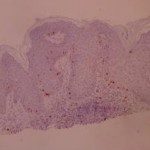

ki-67 staining of reticulo-acanthotic type of SKs.

ki-67 staining of reticulo-acanthotic type of SKs.

ki-67 staining of reticulo-acanthotic type of SKs.

ki-67 staining of reticulo-acanthotic type of SKs.